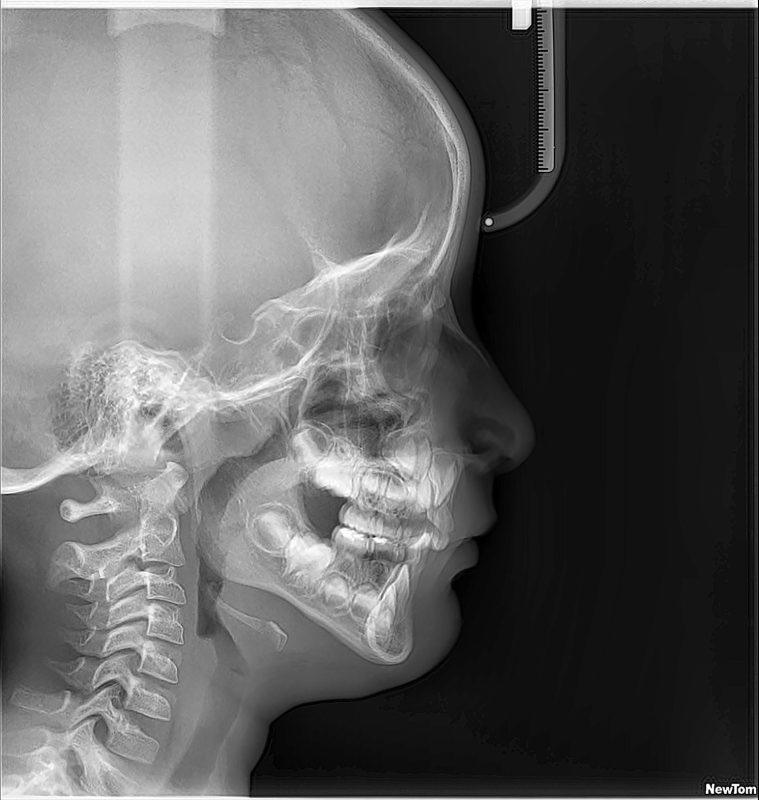

RX SENOS PARANASALES

La radiografía de senos paranasales es una técnica de imagen que se utiliza para examinar las cavidades llenas de aire en los huesos que rodean la nariz, conocidas como senos paranasales. Incluyen los senos maxilares, etmoidales, esfenoidales y frontales. Puede ser realizada para diversos propósitos, como:

CADWELL, CAVUM, WATERS